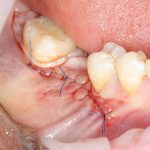

Если на этапе разреза и формирования раны всё сделано правильно, то наложение швов не вызывает особых трудностей. Периостотомия или послабляющие разрезы на периосте не требуются (ни практически никогда не требуются). А сами швы получаются аккуратными и герметичными:

Обрати внимание, что все шовные лигатуры находятся в пределах кератинизированной десны. Это позволяет избежать деформации тканей и лишних рубцов. В наиболее уязвимых местах (около зубов) шовные лигатуры лучше продублировать.

Если бы мне пришлось делать это сейчас, то я бы использовал непрерывный «матрацный» шов. Он удобнее, быстрее в наложении и комфортнее для пациента. Минус — если распускается, то распускается весь. К тому же, его очень неудобно снимать.

Несмотря на то, что уже тогда мы широко использовали непрерывные швы в подобных случаях, здесь я, во-первых, зассал (может распуститься), во-вторых, снятие швов предполагалось в поликлинике по месту жительства пациентки, и мне не хотелось, чтобы там при снятии швов начудили. Как выяснится позже — зря беспокоился.

Неизменно одно — в таких операциях мы использовали и до сих пор используем нерезорбируемые монофиламентные шовные материалы, поскольку они наиболее гигиеничные. Чтобы острые концы нитей не беспокоили пациента, их можно оплавить нагретой гладилкой или гуттаперчевым плаггером.